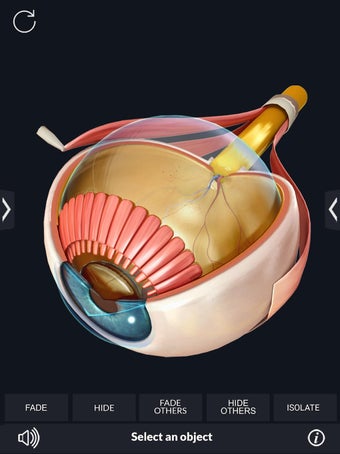

My Organs Anatomy es una aplicación de anatomía 3D gratuita desarrollada por Visual 3D Science para usuarios de Android. Esta aplicación proporciona un modelo 3D altamente realista de los órganos humanos que se puede girar 360°, acercar y alejar, y ver desde cualquier ángulo. La aplicación está diseñada para proporcionar una mirada detallada a la anatomía de los órganos humanos y ofrece varias características para ayudar a los usuarios a explorar y aprender.

La interfaz fácil de usar de My Organs Anatomy permite una navegación sencilla, lo que facilita la selección, rayos X, ocultación y visualización de órganos individuales. La aplicación también incluye un modo de animación, opciones de búsqueda y un panel de información que proporciona información relacionada. Además, la aplicación ofrece pronunciación de audio para todos los términos anatómicos, e incluso los usuarios pueden dibujar o escribir en la pantalla y compartir capturas de pantalla.